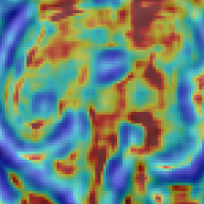

We additionally perform preliminary experiments towards integrating network-based SR components more tightly with an SVR pipeline by investigating the ability of the network to upsample LR voxel intensities that result from an initial volume reconstruction iteration. Successful integration of an iterative (learning-based) SR and volume reconstruction loop will facilitate the well understood mutual benefits of reduced-motion SR input and improved input fidelity for the motion correction task. Qualitative comparison of () LR volume-reconstructed input and resulting upsampled results are found in Fig.3. The benefit of learning the upsampling with modality specific data can be observed to manifest as sharper edge gradients and improved high frequency signal components. The visual quality gap between the baselines and our method can be seen to widen as the prior information required to successfully upsample at larger factors make the task more challenging.

Volume Reconstruction Improvement: In our third experiment we evaluate SVR performance using LR input stacks, upsampled by the considered strategies, before initiating the volume reconstruction task. We additionally perform SVR reconstruction with original HR imagery to provide the “ground-truth” reference brain volumes. Employing the three quality metrics, introduced previously, we evaluate how well super-resolved LR stack reconstructions correspond to the reconstructions due to original high, in-plane, resolution imagery. Table 1 reports PSNR, SSIM and cross-correlation metrics for volume comparison (SR strategy with respect to “ground-truth” volume) for the patients that define the MRI stack test set. Super-resolving the LR input data with the proposed learning based approach can be observed to facilitate reconstruction improvement, across the investigated metrics. Visual evidence supporting this claim is found in Fig. 4 (best viewed in color). Fig. 4 displays 2D slices of patient fetal brain reconstructions resulting from the original HR input-imagery (far left) and identically spatially-located slices (a) resulting from (b) LR imagery (half the in-plane resolution), (c-d) input using naïve up-sampling strategies and (e) our 3D MRI CNN upsampling. Corresponding Structural Dissimilarity (DSSIM) error heatmaps (second row) provide improved visual spatial congruence between HR ground-truth and our method, supporting the claim that utilizing sensor specific priors is of marked benefit for the task of MRI fetal brain reconstruction from LR imagery.